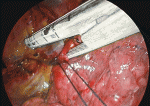

区域切除手術手技が肺葉切除と異なる点は1)剥離して露出する構造物(肺血管,気管支など)が肺葉切除より細く小さくなること,2)ステープラーを通しにくくなること,3)葉間よりも区域間が立体的で複雑になることから切離面の同定と正しい区域間での切離が難しくなることが挙げられる.単孔式手術では,剥離・切離する組織に適切なテンションをかけること,組織を切離する際は,剥離鉗子やエネルギーデバイスによる剥離操作で血管など重要臓器から切離する組織を離して剥離した部分のみを切離すること,血管や気管支を切離するときは肺を剥離・切離しやすい方向に移動させて(Move the ground)術野展開を行うことが大切である.スコピストは斜視鏡をうまく使用して術者の手に干渉せずに良い視野を見せるように操作することが安全に手術を行うコツである.